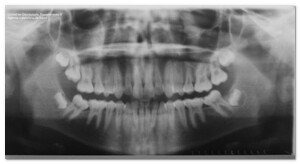

El estudio de los maxilares atróficos, el papel de la implantología en la reconstrucción de los defectos post-traumáticos, la regeneración de las recesiones gingivales mediante el plasma, las posibilidades de predicción y éxito de los implantes, tanto desde un punto de vista clínico como estético, la mesoterapia oral como herramienta eficaz para el rejuvenecimiento facial, o la publicación de un protocolo de injertos en senos maxilares, fruto del consenso de Vitoria 2008, configuran el eje central del programa científico.